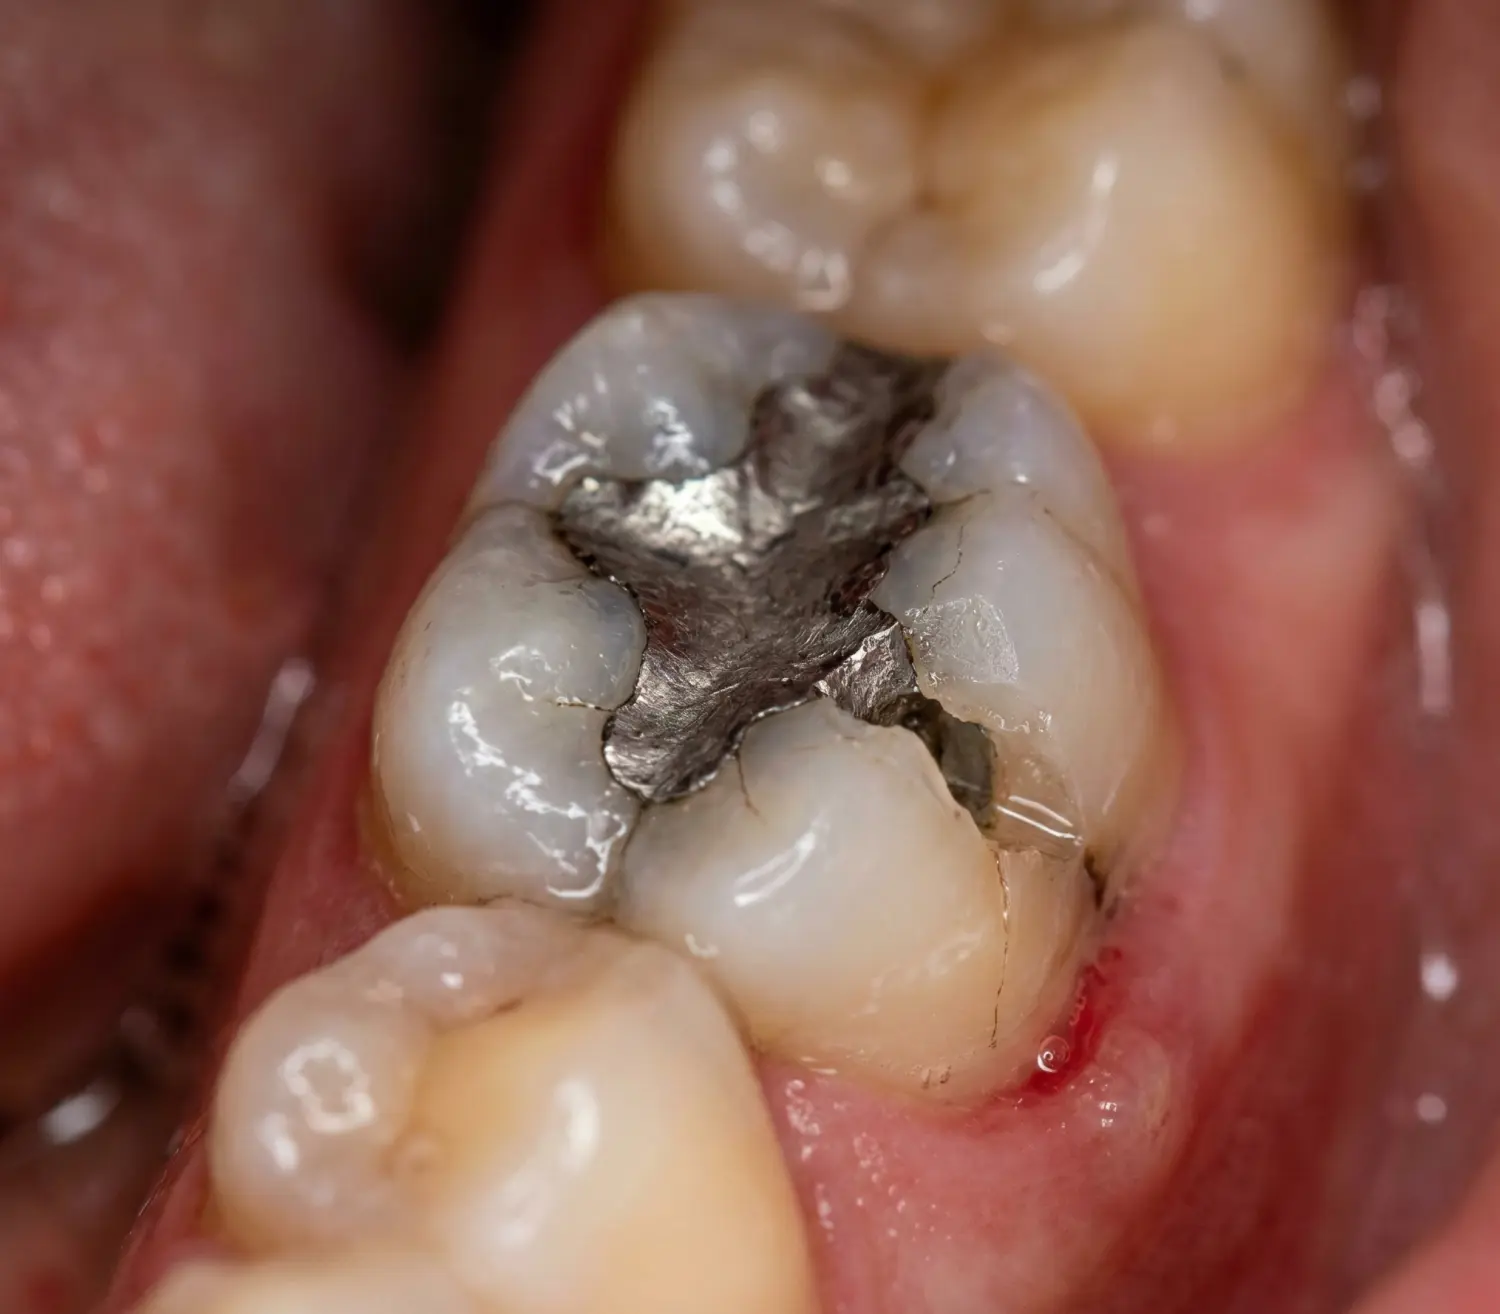

Dolgunun Eskimesi

10–15 yılı aşan dolgular malzeme yorgunluğu nedeniyle kırılmaya eğilimlidir.

Sekonder Çürük

Dolgu kenarında oluşan çürük, dişin yapısını zayıflatarak kırığa zemin hazırlar.